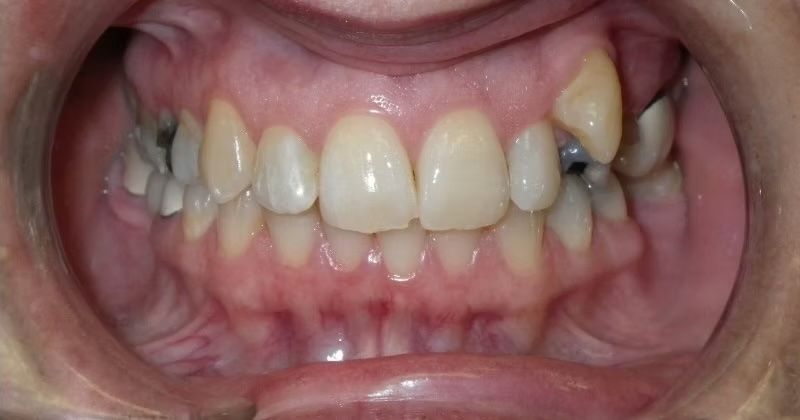

AMBER

Amber, began treatment with Dr. Bret because she didn't like that her front teeth overlapped each other. She had narrow top and bottom dental arches with severe crowding of her upper and lower teeth. She was treated with braces on the upper and lower teeth, and we used the braces to widen the smile. What a change!